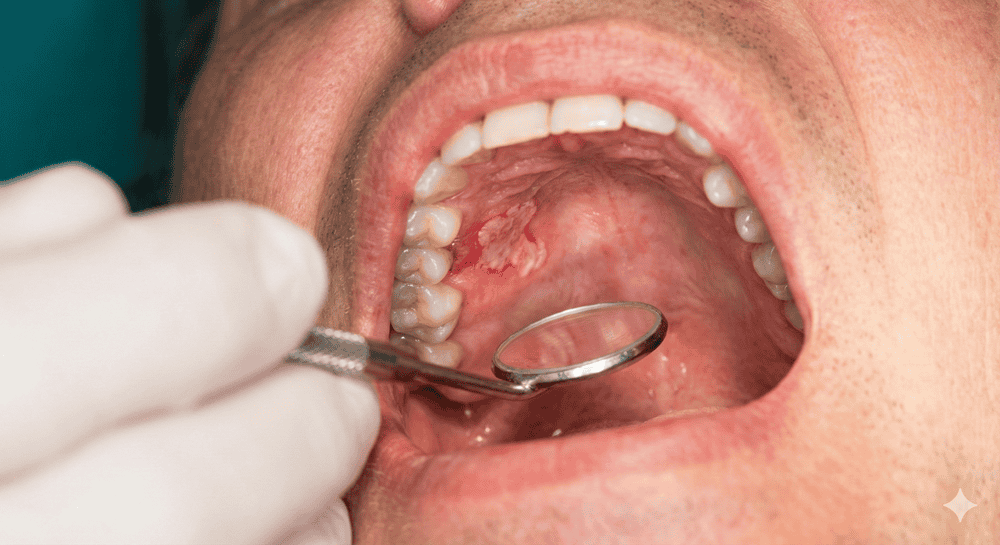

عکس سرطان سقف دهان

الف) زخمهای دهانی پایدار (Ulcers)

شایعترین علامت، زخمی است که روی کام ایجاد میشود. برخلاف آفت که دردناک، سطحی و دارای هاله قرمز است و طی ۱۰ روز خوب میشود، زخم سرطانی:

- بیش از ۲ هفته باقی میماند.

- لبههای برجسته و سفت (رول شده) دارد.

- مرکز زخم ممکن است خاکستری یا زرد باشد و به راحتی دچار خونریزی شود.

- اریتروپلاکیا (لکههای قرمز): نواحی قرمز مخملی و براق در سقف دهان. این ضایعات بسیار خطرناکتر از لکههای سفید هستند و پتانسیل بالایی برای بدخیمی دارند.